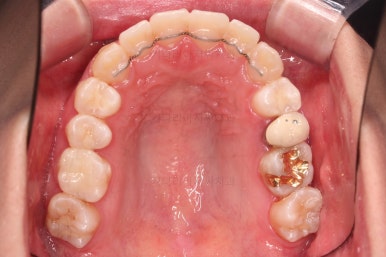

부산비대칭교정 마무리 때의 입안의 모습입니다.

가지런한 느낌은 좋지만 정중선 당연히 약간 안맞고요.

폭도 100%는 안맞아서 어금니쪽이 약간 애매한 교합이기도 했습니다.

하지만 이정도의 비대칭 상황에서 이정도의 교합은 교정만으로 할 수 있는 베스트가 아닌가 생각됩니다.